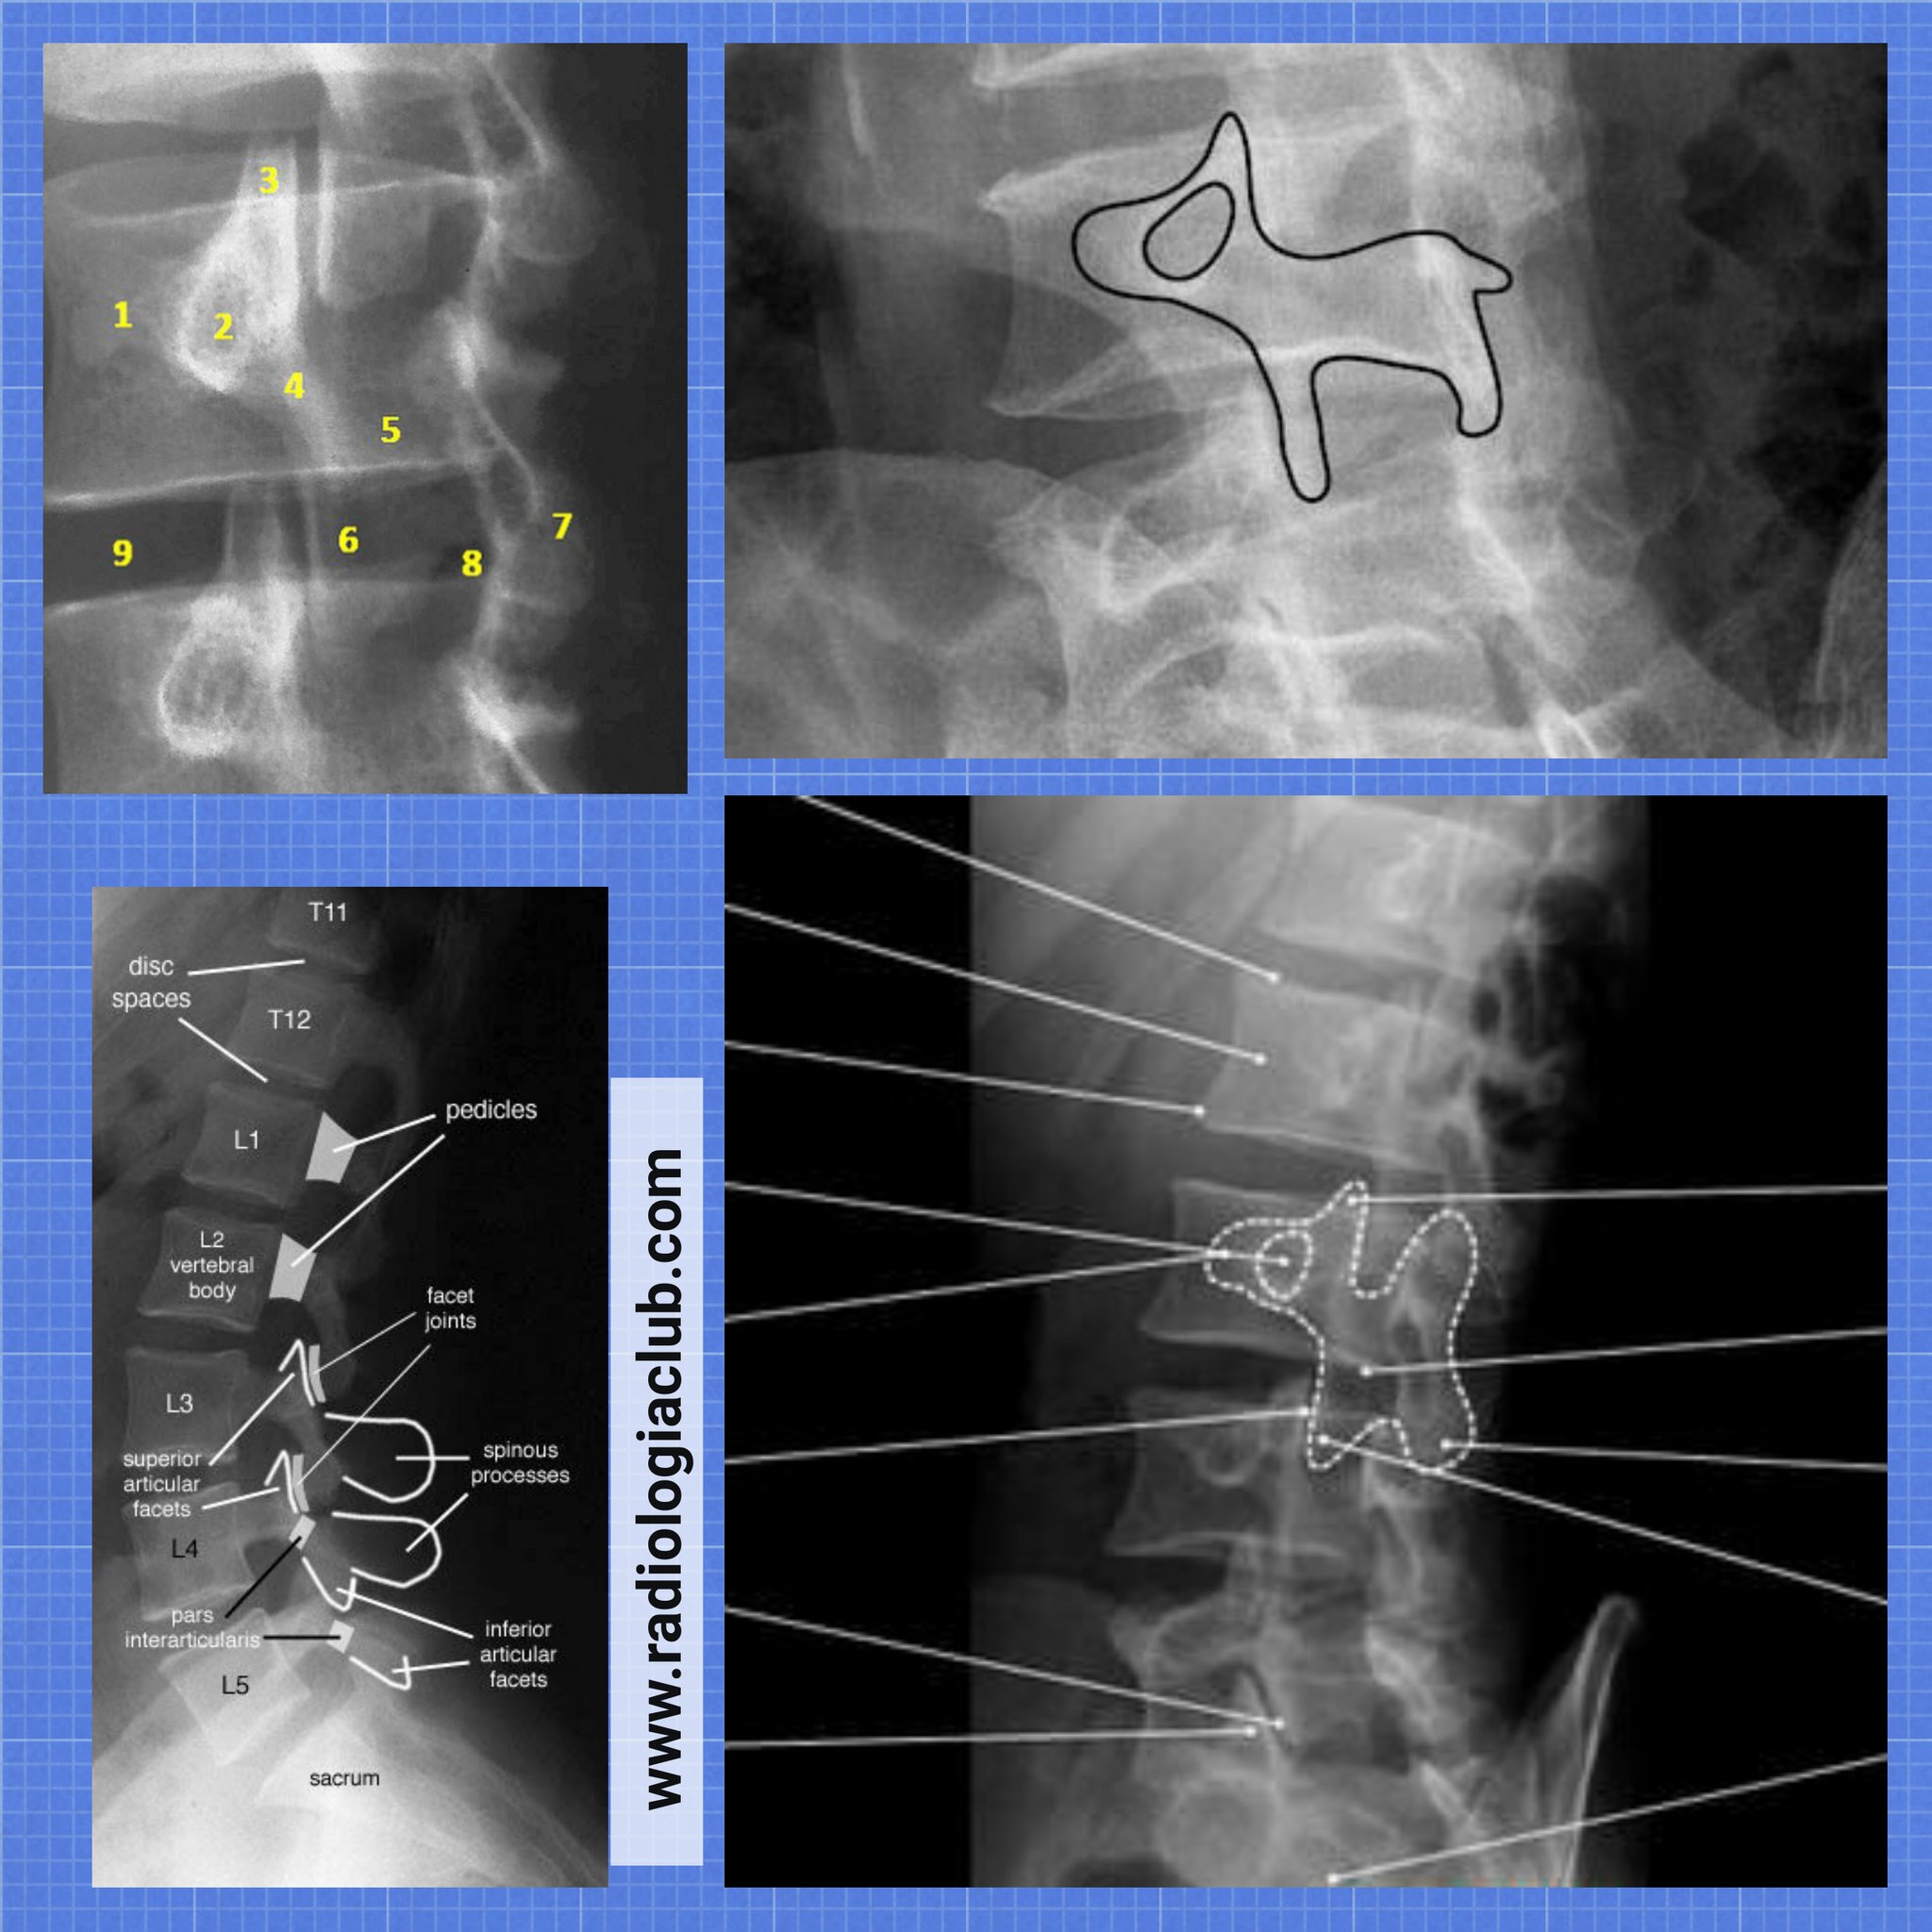

Com interpretar l´imatge del gosset

Imatge del "gosset" en una projecció obliqua de Columna Lumbar correcta